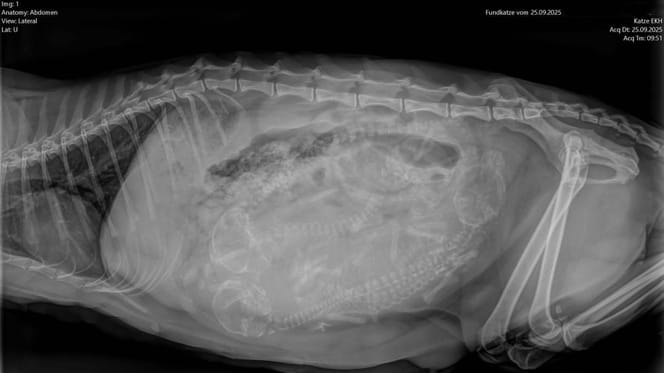

Jak w przypadku wszystkich nowo przyjętych zwierząt, opiekunowie przeprowadzili dokładne badanie. Zauważono coś niepokojącego: kotka poruszała się sztywno, jakby odczuwała ból. Aby się upewnić, wykonano prześwietlenie, a wynik był druzgocący.

Kości kotki wykazywały wyraźne deformacje – typowy objaw kotów tej rasy, będącej wynikiem hodowli obciążającej cierpieniem.

Urocze, złożone do przodu uszy, które wielu ludzi uważa za tak czarujące, są wynikiem mutacji genetycznej. Powoduje ona przewlekłe uszkodzenia kości i stawów przez całe życie zwierzęcia.

Mutacja, która odpowiada za złożone uszy, wpływa na całą strukturę chrząstek i kości. Wiele zwierząt cierpi już wcześnie na artrozę, kulawiznę i silne bóle.